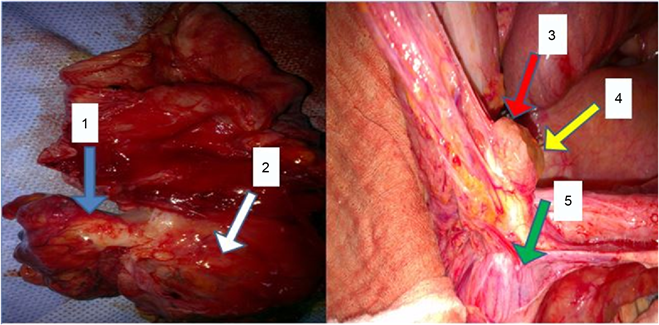

Surgery was performed on all the patients. Surgical exploration in one patient found a gelatinous collection attached to the tip of the appendix which was thick

Figure 1. Preoperative images: 1―Posterior view of the appendix; 2―Posterior View of the caecum; 3―anterior view of the appendix; 4―Gelatinous collection attached to the tip of the appendix; 5―anterior view of the caecum.

and infiltrated in its entirety as well as the cecum. Two patients had a thickened appendix and cecum; a deep thickened cecal pouch with an appendix in the internal lateral-cecal position. For the fourth patient, the tip of the appendix was implanted within the Psoas muscle, the release of the appendix revealed the presence of mucus in retroperitoneal cavity. The presence of a tumor of the appendix extending to the caecum was found in another patient. For the last one, the appendix was phlegmonous, perforated at its point with the presence of gelatinous fluid. There was an extensive carcinosis in the mesentery and parietal peritoneum.